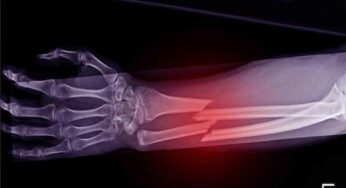

Bones Health : చ‌లికాలంలో వీటిని తింటే మీ ఎముక‌లు సేఫ్‌.. లేదంటే విరిగిపోతాయి జాగ్ర‌త్త‌..!

Bones Health : చ‌లికాలంలో ఆహ్లాద‌క‌ర‌మైన వాతావ‌రణంతో పాటు అనేక రకాల అనారోగ్య స‌మ‌స్య‌లు కూడా మ‌న‌ల్ని వెంట‌డ‌తాయ‌ని చెప్ప‌వ‌చ్చు. చ‌లికాలంలో మ‌న‌ల్ని వేధించే అనారోగ్య స‌మ‌స్య‌ల‌ల్లో…